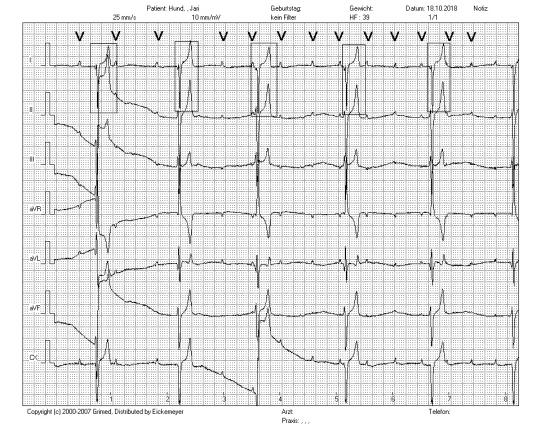

Nun wird ein EKG (Elektrokardiogramm) erstellt. Bei dieser Untersuchung werden die elektrischen Ströme im Herzen dargestellt, welche die Pumpaktion des Organs koordinieren. Das EKG zeigt, dass der Hund an einem sogenannten "Atrio-Ventrikulären Block 3. Grades" leidet: Normalerweise entsteht im sogenannten Sinusknoten im rechten Herzvorhof der elektrische Impuls, welcher zur Kontraktion des Herzen führt. Dieser Impuls wird koordiniert bis in die Ventrikel (Hauptkammern) des Herzen fortgeleitet, so dass kurz nach der Kontraktion der Vorhöfe und somit Füllung der Ventrikel eine Kontraktion der Ventrikel erfolgt, damit das Blut ausgestossen werden kann.

Bei Jari sieht man im EKG nun in regelmässigen Abständen zwar eine P-Welle ("V" im untenstehenden EKG), welche den elektrischen Impuls im Vorhof darstellt. Dieser wird aber nicht von einem entsprechenden Impuls des Ventrikels gefolgt; stattdessen erfolgt in längeren Abständen und nicht koordiniert mit den P-Wellen ein sogenanner "ventrikulärer Escape"-Impuls (rechteckiger Rahmen im untenstehenden EKG), welcher im Ventrikel selbst gebildet wird. Ursache dafür ist, dass der elektrische Reiz vom Vorhof nicht mehr in den Ventrikel geleitet wird, worauf dieser zu dieser Notmassnahme greift, damit überhaupt noch Blut gefördert werden kann. Ganz offensichtlich führt das bei Jari dazu, dass phasenweise der Blutdruck nicht mehr gehalten werden kann und der Hund kollabiert.

Die Pumpaktion des Herzmuskels wird durch einen elektrischen Taktgeber und entsprechende "Stromleitungen" ausgeklügelt gesteuert. Der im rechten Vorhof sitzende sogenannte Sinusknoten löst je nach Bedarf und u.A. gesteuert vom vegetativen Nervensystem den Impuls zur Herzkontraktion aus. Dieser Impuls ist im EKG als "P-Welle" erkennbar (im untenstehenden, normalen EKG mit "V" gekennzeichnet). Der Reiz wird dann via AV-Knoten über Reizleitungsbahnen in die Hauptkammern geleitet und löst die Kontraktion der Ventrikel aus; dieser Impuls ist als "QRS-Komplex" im EKG erkennbar (im untenstehenden EKG umrahmt). Der QRS-Komplex erfolgt also im Normalfall unmittelbar und regelmässig nach einer P-Welle. Bei Jari ist diese Überleitung gestört, die Reize des Sinusknotens erreichen die Kammer nicht. Das Herz greift in der Folge zu einer Notmassnahme, um überhaupt noch Blut fördern zu können: es aktiviert alternative, im Herzen weiter unten liegende Rhythmusgeber, welche normalerweise vom Sinusknoten übersteuert werden. Dieser sogenannte "Ventrikuläre Escape-Rhythmus" ist aber deutlich langsamer als der normale Rhythmus vom Sinusknoten und ist nicht mit der Vorhofaktivität koordiniert, weshalb weniger Blut gefördert wird und der Blutdruck unter Umständen nicht mehr aufrecht erhalten werden kann. In den meisten Fällen eines AV-Blockes 3. Grades kann keine konkrete Ursache für das Problem eruiert werden.